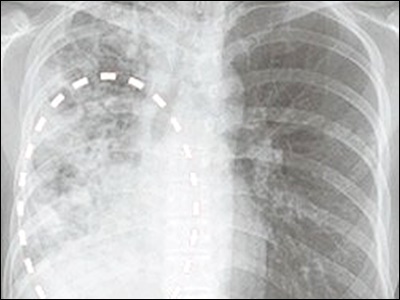

결핵 진단을 위해서는 피부 검사, 가슴 X-선, 결핵균 검사 등의 검사가 필요합니다. 이러한 검사를 통해 정확한 진단을 받을 수 있습니다.

결핵은 폐결핵, 림프절 결핵, 뼈 결핵 등 다양한 형태로 나타날 수 있습니다. 각각의 증상을 상세히 분석하여 이해할 수 있습니다.